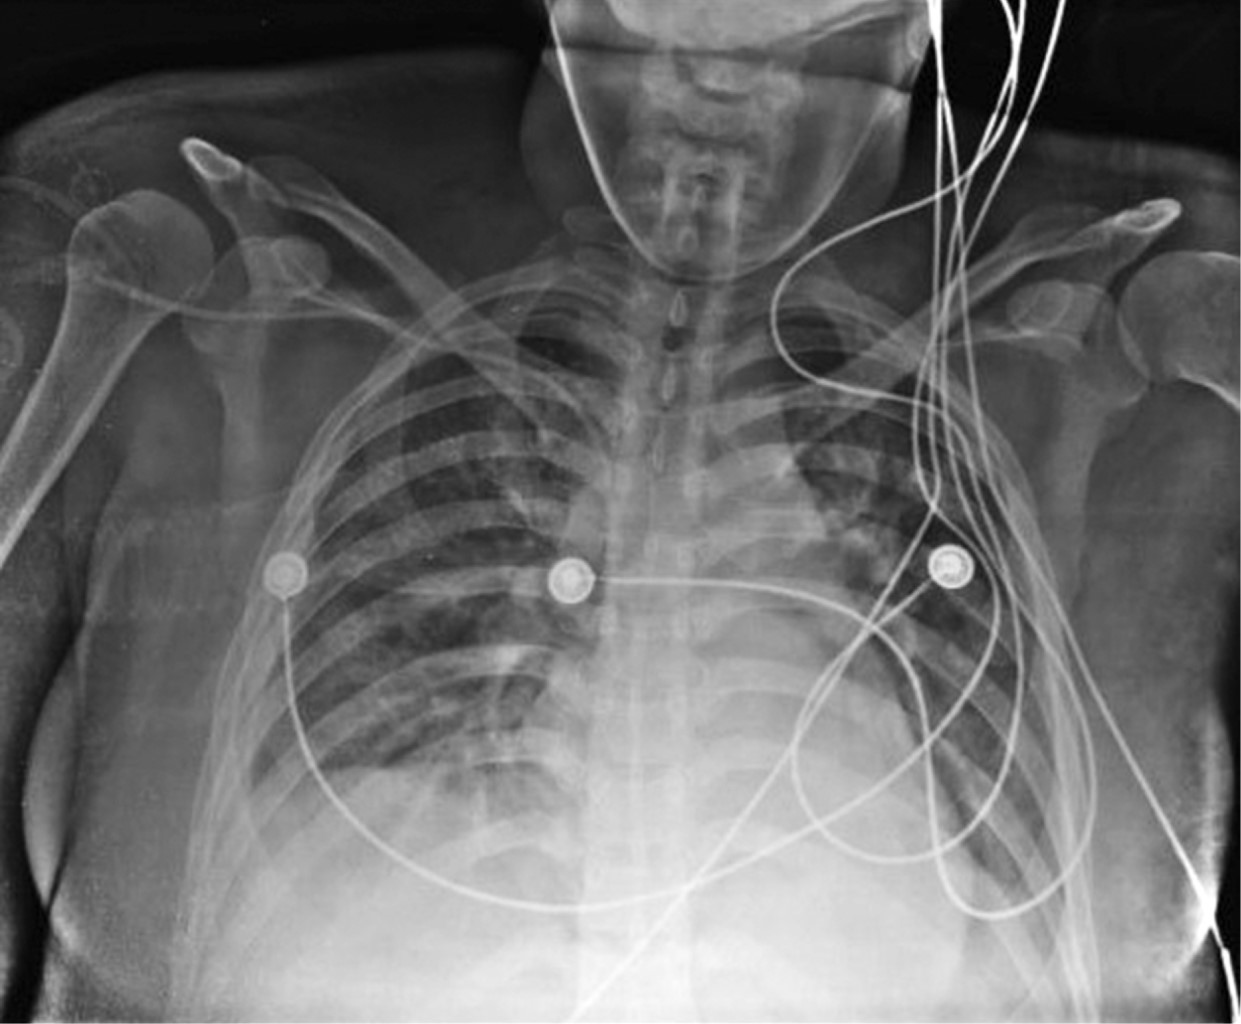

Se traslada a su institución de envío donde se toma radiografía de control con adecuada expansión pulmonar bilateral (Figura 4).